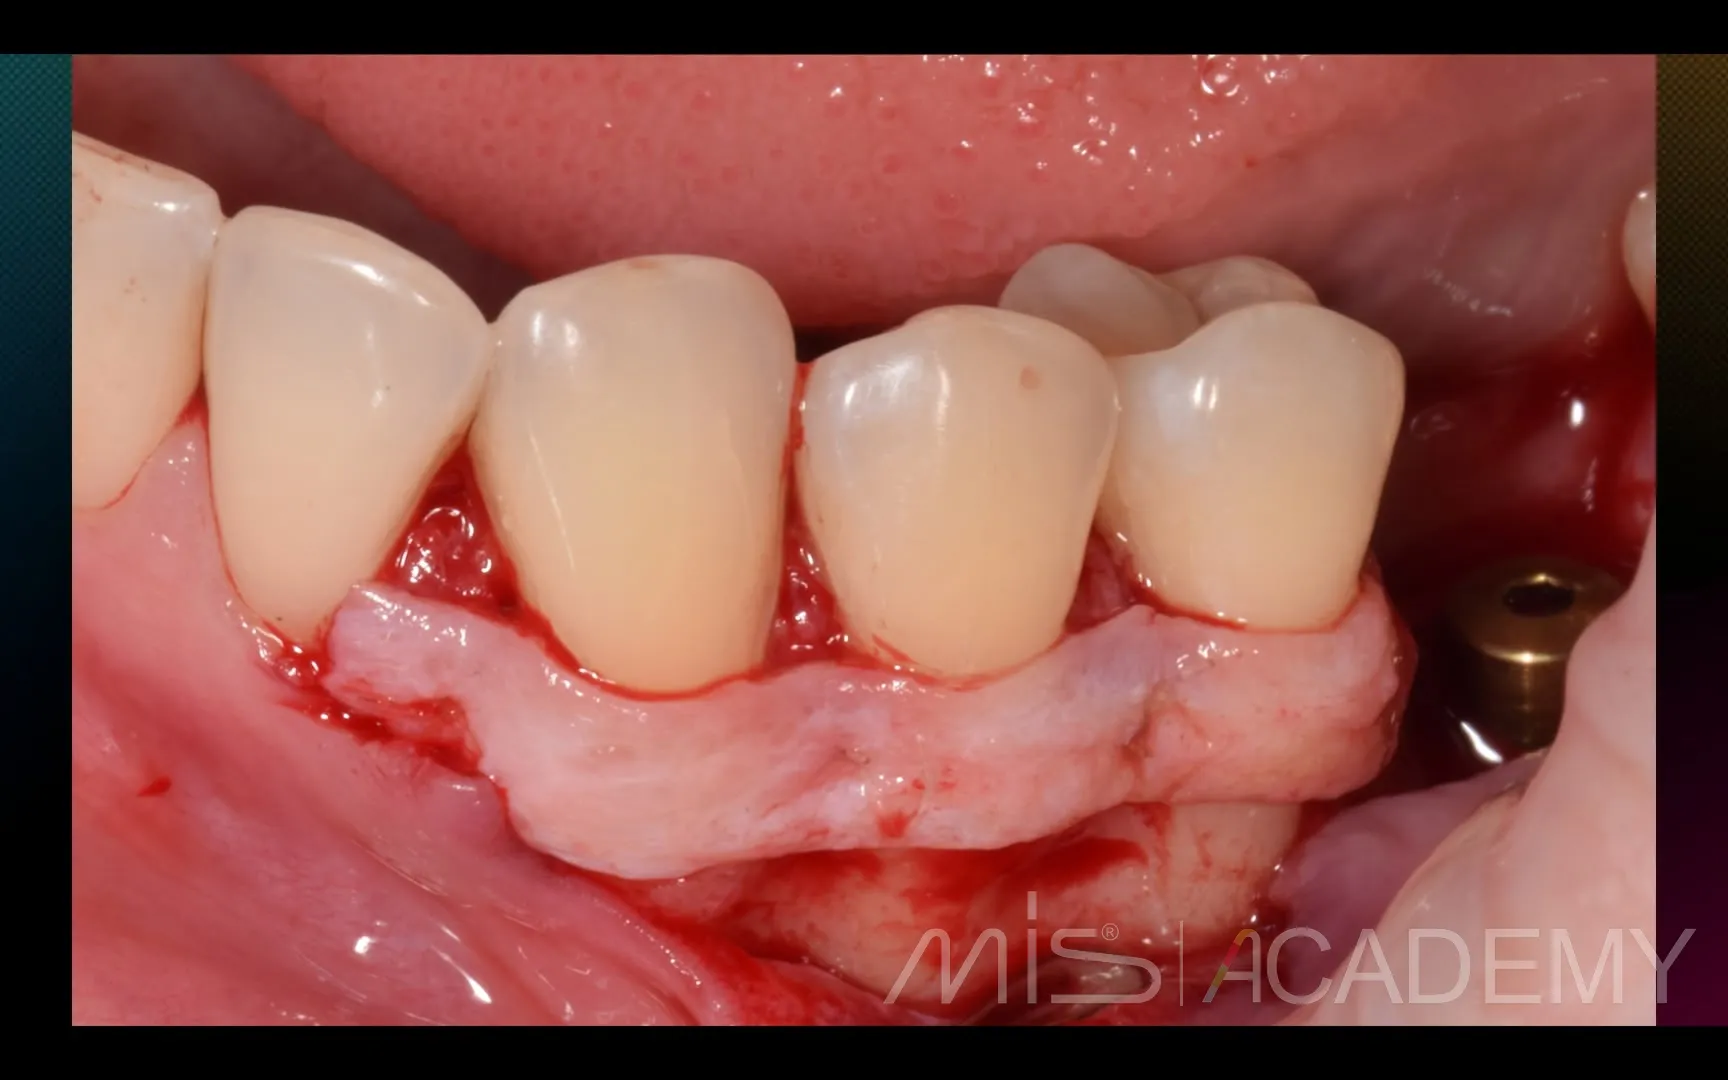

Промежуточный результат клинического кейса одномоментного закрытия рецессий и установки имплантата MIS C1 с CONNECT абатментом.